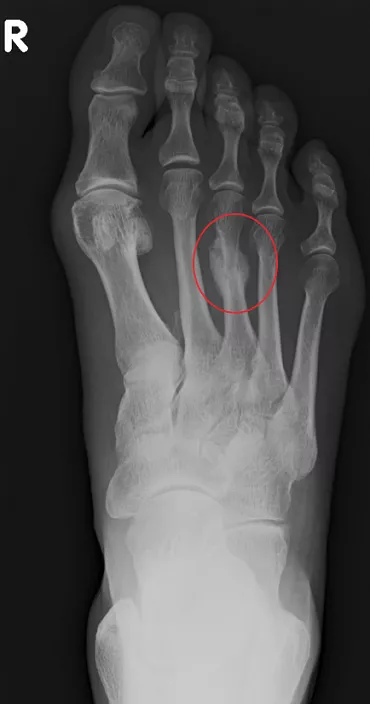

– Co, jakie kości, łamiemy najczęściej z powodu przeciążenia?

– Biegacze najczęściej łamią kości śródstopia, przede wszystkim drugą, trzecia i czwartą. Nieco rzadziej zdarzają się złamania kości w podudziu, piszczelowej i strzałkowej, rzadko złamania szyjki kości udowej i miednicy, które są najniebezpieczniejsze i wymagają najbardziej radykalnego leczenia, łącznie z operacją.